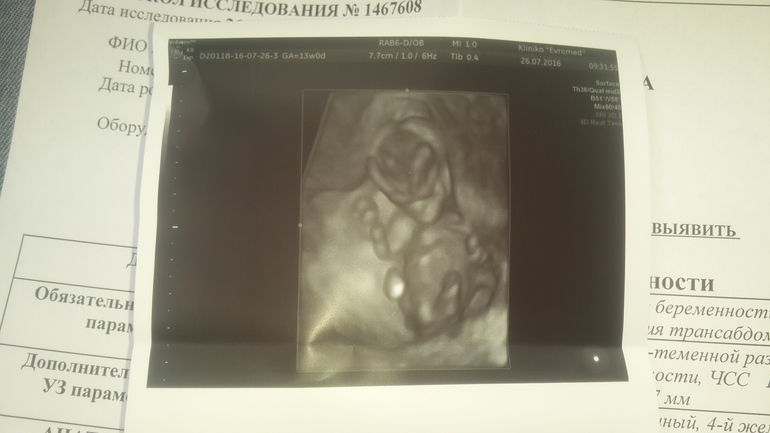

Беременность- 1 триместр ( только до 10 недель)Здравствуйте мои дорогие! Вот и прошло 13 недель! Первый свой скрининг решила делать в платном центре,т.к. по отзывам узи в ЖК не порадовало! Заранее узнала что не знаю за сутки есть жареное, сладкое,соленое и копченое,поэтому вечером покушала вареников и легла спать! Регистраторы подобрали время узи в 9.15 утра,а потом сразу кровь! На узи увидела как мой малыш активно дрыгает ручками и ножками (подвижный ребеночек),узистка показала ручки,ножки, и сердце...а в нем в левом желудочке синдром "гольфного мяча"....в целом все остальное в роде в норме. На прием к Г только 3 августа,поэтому пока переживаю,хоть и прочитала что этот синдром не является пороков. Тем не менее помогите расшифровать результаты пожалуйста(больше волнует кровь ). А еще мне сделали фото 4D (там простите какое то зло (это я любя конечно))! !!